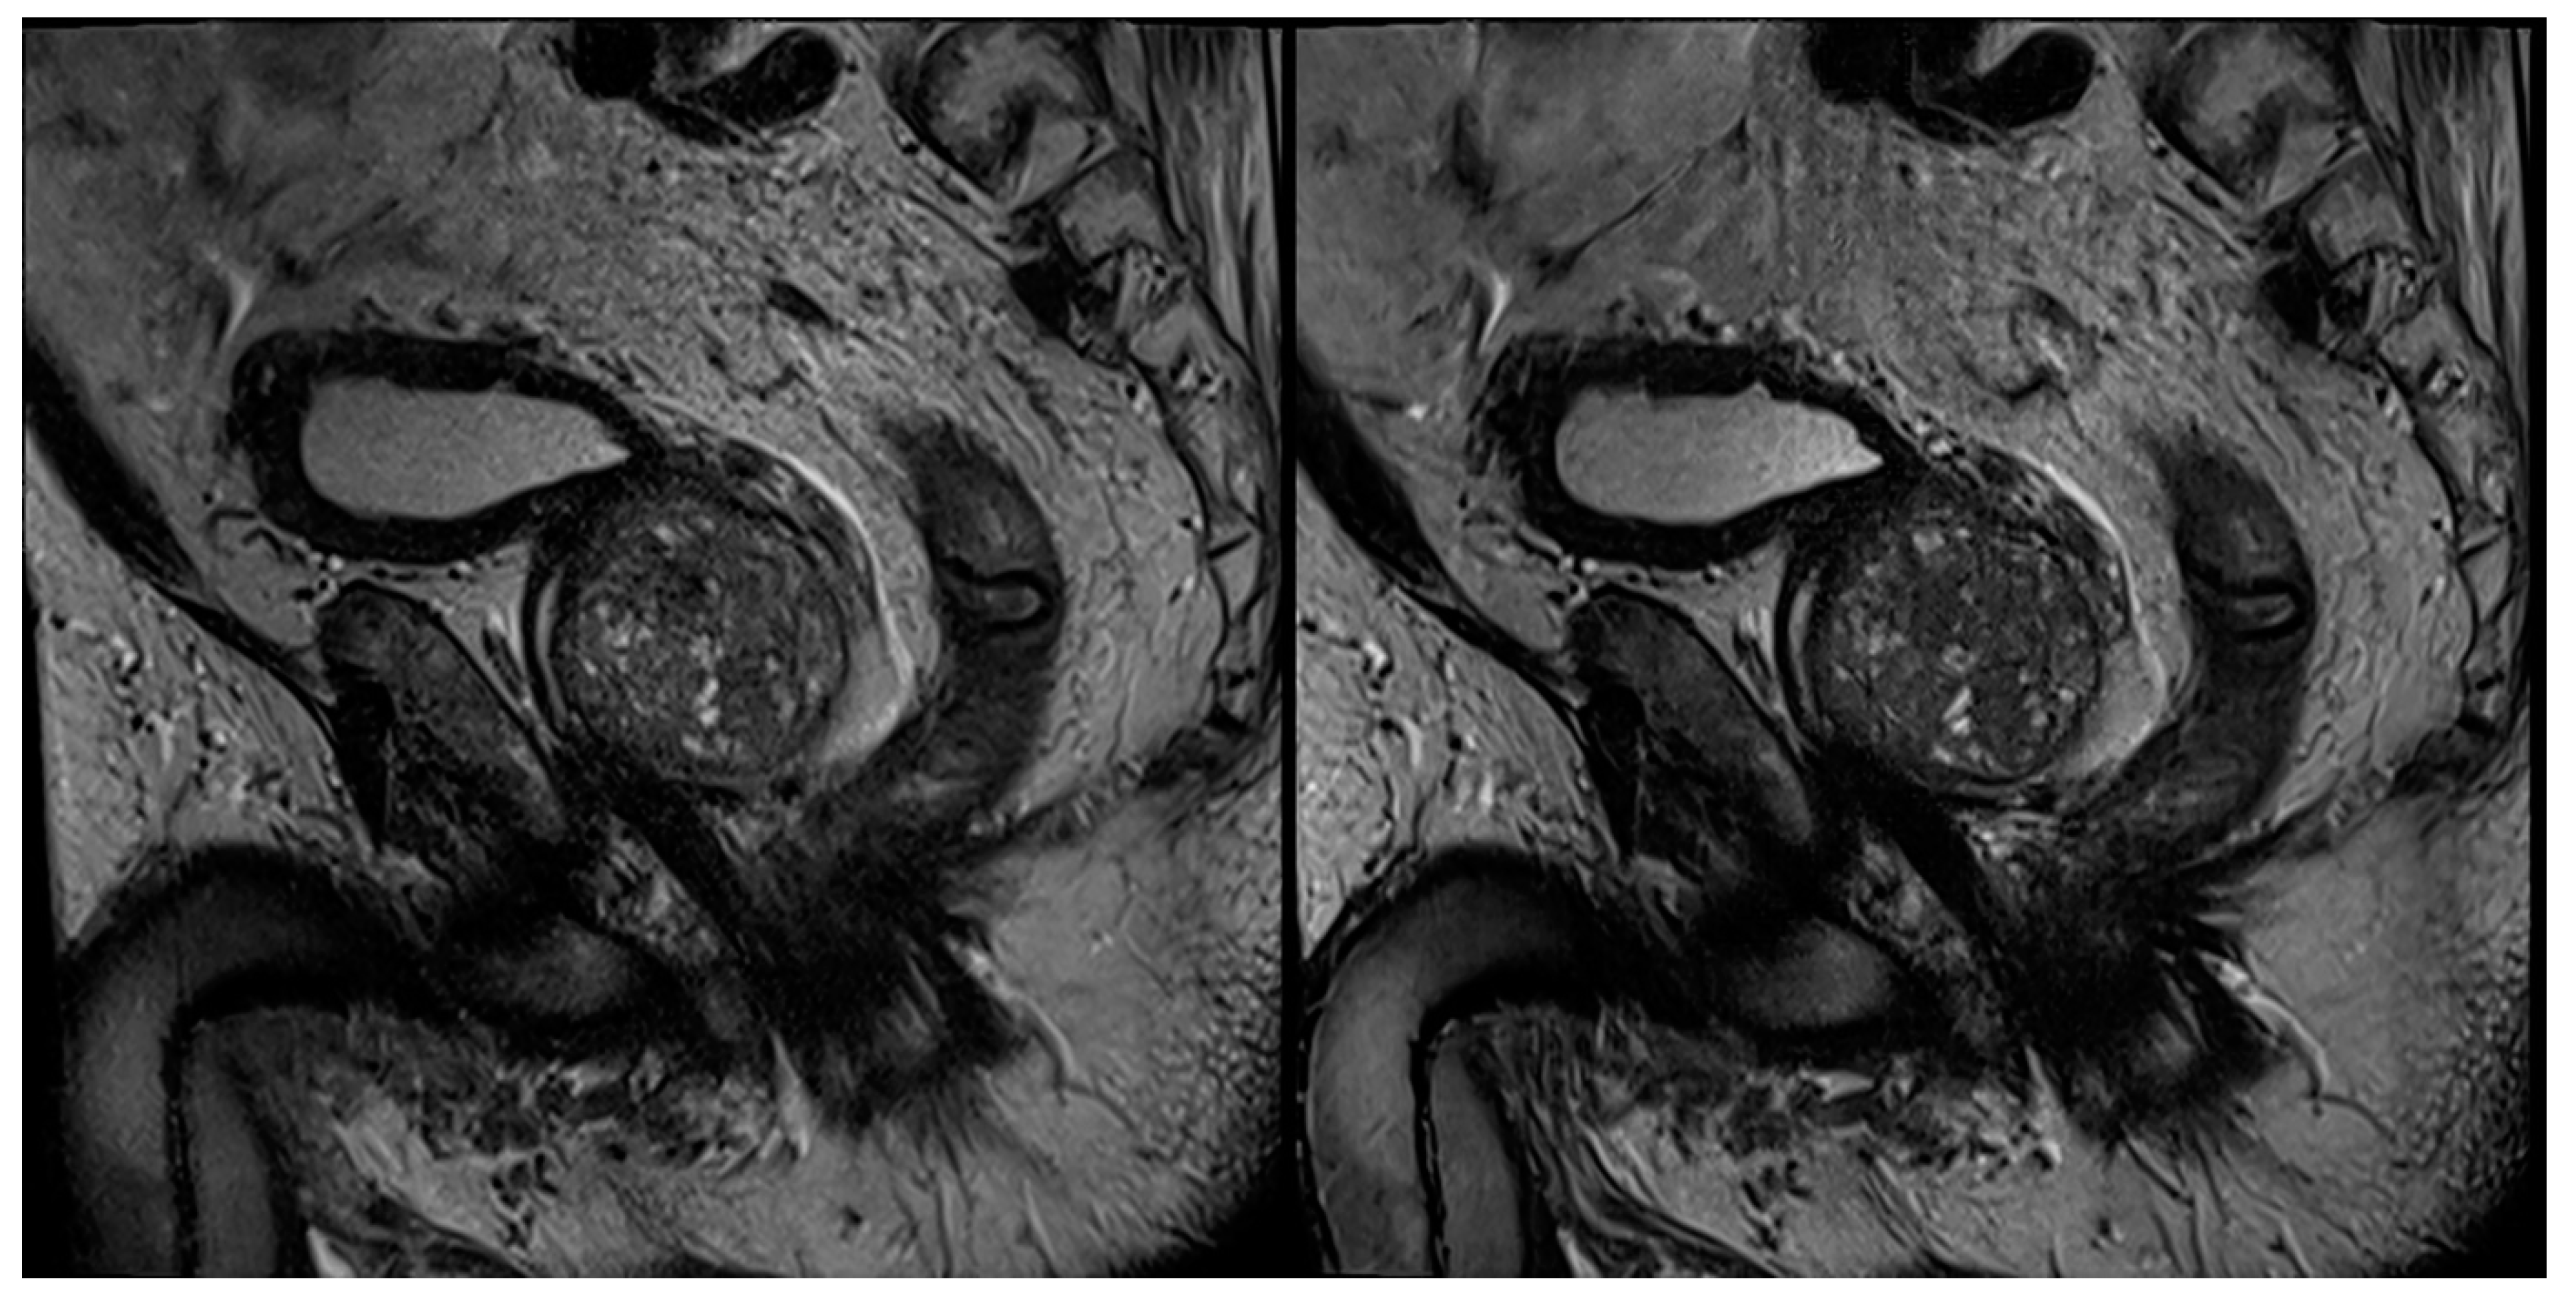

Figure 4. A 67-year-old male patient with suspicion of prostate cancer. Example of coronal standard T2-weighted TSE imaging (T2S) on the left-hand side and deep learning–reconstructed (T2DLR) imaging on the right-hand side. Advantages of T2DLR are demonstrated, regarding less image noise and improved delineation of anatomic structures.